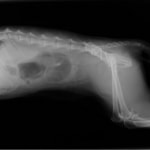

ペルシャ猫 11ヶ月齢 雄

他院にて左大腿骨遠位の成長板骨折(salter-harrisⅠ型)が認められており、治療相談を目的として来院。当院にて、キルシュナーワイヤーを用いたピンニングにより骨折部位の整復を行いました。術後の経過は良好で、現在も経過観察中です。

術前レントゲン